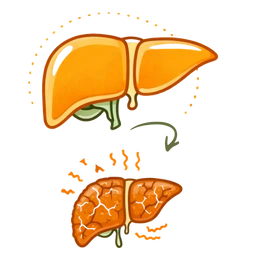

What is Fatty Liver Disease? (Hepatic Steatosis) & its Types

Fatty liver disease (hepatic steatosis) is a condition characterized by the buildup of too much fat inside liver cells. Our liver can have a little fat normally. It is when the fat is more than 5% to 10% of the liver weight that it is treated as a problem requiring a doctor’s intervention. Therefore, a person needs to be identified at the initial stage in order to have a good fatty liver therapy.

Fatty liver stages (reversibility):

- Grade 1 (Simple Fatty Liver):Presence of fat accumulation without inflammation. Very much reversible through diet and Ayurvedic medication.

- Grade 2 (Moderate):Higher fat content with a slight inflammatory state. Hence, the only condition that can be reversed with strict care and giving up bad habits.

- Grade 3 (Severe/Fibrosis):Where the inflammatory reaction is accompanied by tissue damage. Therefore, it is hard to reverse but the condition can be controlled through a good liver detox.

- Cirrhosis: It is the last stage where the liver has been extensively scarred and totally lost the ability to function.

Risks & Complications of Untreated Fatty Liver Disease

Even if you have been diagnosed with Grade 1 or Grade 2 Fatty Liver, ignoring it is risky. What initially may look like a simple lifestyle issue can, if the liver detoxification is not initiated in time, without one’s knowledge, develop into life, threatening conditions.

Cirrhosis

It is a condition of irreversible scarring where the liver becomes hard, shrunken, and the damage is permanent.

Liver Failure

The organ completely ceases to function, thus, a liver transplant becomes the only option.

Liver Cancer (HCC)

Long, term inflammation and damage that is not treated will greatly increase the risk of liver cancer.